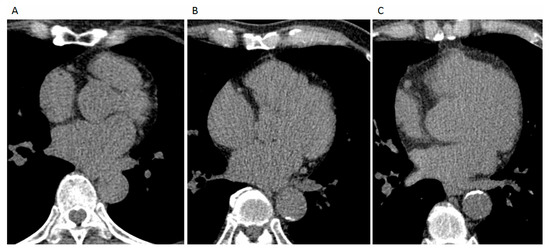

2.3. Semi-Automatic Quantification of Three-Dimensional (3D) Thoracic Aortic Calcification